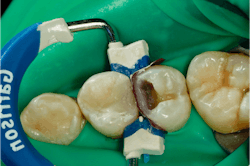

I always build my marginal ridge and interproximal wall first. Here you can see my first increment of Tetric PowerFill. Because the measurement from the gingival floor to occlusal surface was 4 mm, this wall is built up in only one increment (figure 7).

This is cured for three seconds using my Bluephase PowerCure light on 3s mode. Once the first increment is cured, I fill the rest of the preparation with Tetric PowerFill, shape, and cure (figure 8).